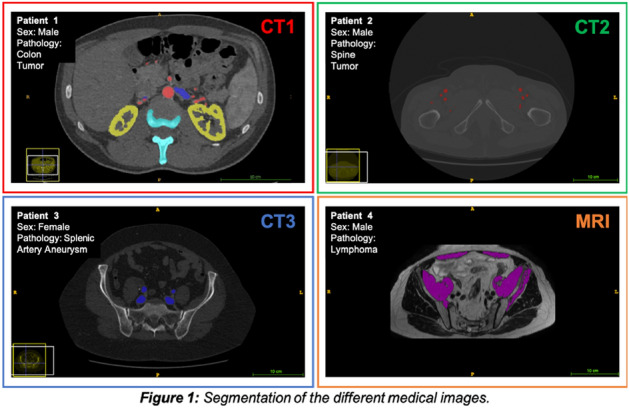

Aims: 3D modelling technology is rapidly gaining interest in various fields of surgery. It can be used for operative planning and navigation, as well as surgical education and patient interaction. It allows for depiction of complex anatomical relationships in a more comprehensible way than traditional radiological images. However, it also has potential to become a tool facilitating gaining further understanding of surgical pathology by allowing to display and analyse imaging data in a new way. Tumour deposits are a challenging entity. They are currently being closely investigated with an aim to develop understanding of their role in colorectal cancer spread. It is an ever evolving concept which requires further research to fully appreciate the origin and significance of tumour deposits. We applied the novel 3D modelling technology to illustrate tumour deposits in colorectal cancer.

Methods: 3D virtual models were created through manual segmentation of CT and MRI scans obtained according to protocols routinely used in colorectal cancer staging. No extra patient time or preparation were needed. CT and MRI images were analysed by Gastrointestinal Radiologist to delineate the tumour and provide the cancer staging. Manual segmentation was then performed in 3D Slicer, an open-source, free software used for creation of three-dimensional anatomical models. Additional post-processing was applied in MeshLab or Blender.

Results: Ten 3D models depicting tumour deposits in colorectal cancer were created. Models of right- and left-sided bowel cancer with tumour deposits were derived from CT scans, while those of rectal cancer—from MRI scans. 3D models depicted bowel with the tumour and tumour deposits, relevant vasculature and lymph nodes, as well as surrounding structures as required. Models can be manipulated to allow for most comprehensible inspection of different anatomical structures and relationships. The transparency of each structure can be changed. The morphological appearance of tumour deposits and their relation to vessels can be readily appreciated. The morphological differences between the tumour deposits and lymph nodes, both benign and metastatic, can also be evaluated.

Conclusions: This work follows on from our previous experience with exploration of 3D modelling technology to map tumour deposits in rectal cancer, based on rectal MRI images. This innovative technology shows a huge potential to enhance our understanding of surgical pathology. It can provide a welcome assistance in exploring new concepts and developing new theories. It can facilitate communication and discussion around the evolving concepts. It is a versatile novel tool which can be successfully applied for depiction of tumour deposits in any part of the bowel. Here we showed its feasibility for the use in left- and right-sided bowel cancer, in addition to previously explored rectal cancer. It can utilise modalities commonly used in colorectal cancer staging – CT and MRI, which renders it clinically applicable. While there is an ongoing debate on the correct classification of tumour deposits and their full significance in metastatic process, as well as their prognostic value, 3D technology can facilitate familarisation with their appearance. It can also become an educational tool both for radiologists and surgeons and a valuable adjunct in the multidisciplinary management of colorectal cancer.